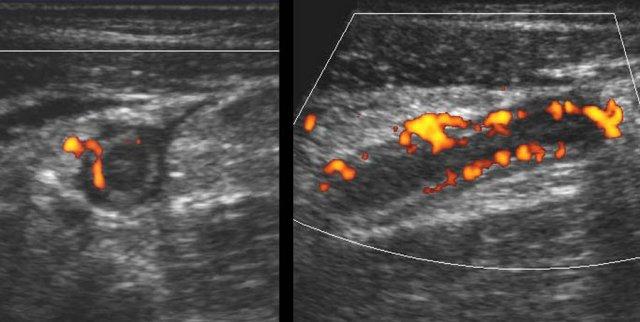

Tăng sinh mạch máu

Như đã đề cập trước đó, sự tưới máu thành ruột thừa ban đầu giảm do áp lực trong lòng ruột thừa tăng cao.

Tuy nhiên, áp lực cao này sẽ giảm nhanh trở lại do niêm mạc ruột thừa bệnh lý không còn khả năng duy trì sản xuất dịch bình thường.

Kết quả là, kết hợp với đáp ứng viêm mạnh mẽ, tình trạng tăng sinh mạch máu phản ứng mạnh sẽ xảy ra nhanh chóng: đầu tiên trong mô mỡ xung quanh và ngay sau đó cả trong thành ruột thừa.

Vì đây là thời điểm bệnh nhân thường tìm kiếm sự trợ giúp y tế, đây là hình ảnh siêu âm quen thuộc nhất của ruột thừa viêm.